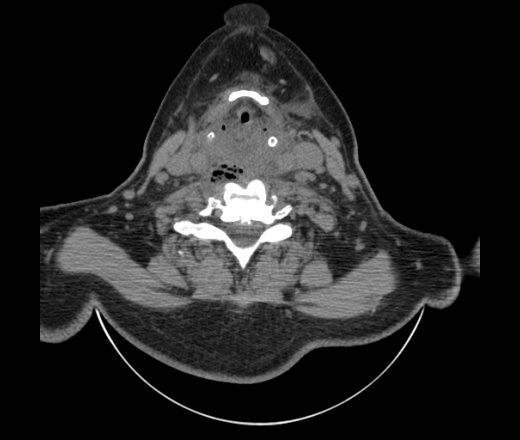

Женщина поступила в х/о спустя 4 дня после того как при употреблении карася подавилась костью.

Наличие газа в средостении на протяжении тел С2-С6 (медиастинальна эмфизема); рыбная кость на уровне тела С6.

При всем уважении, но говорить о медиастинальной эмфиземе, оценивая мягкие ткани шеи, как-то слишком резко. На мой взгляд, это ретрофарингеальное пространство.

Эвакуировали почти 100мл гноя. Но кость не смогли найти. Думаю что она даст дальнейшее ослоднение. Эндоскопически за черпалонадгортаной звязкой не смогли зайти в пищевод, все мягкие ткани отечные, просвет пищевода сдавлен. По всей видимости параэзофагеальная клетчака тоже задействована. Эмпиема, если ее можно так назвать, незнаю как правильно дошла до уровня яремной вырезки. Чем закончиться напишу. Ждем медиастинита.

Согласен с Вами; конечно, наличие газа в клетчатке ретрофарингеального пространства (затмение с опечаткой..). К сожалению, процесс "продвигается" к медиастиниту. Но почему никто, не отмечает наличие рыб. кости; или это для Всех очевидно?

Кость то мы сразу выявили, размеры где то 17*2мм, но ее так и не получается найти в этой каше